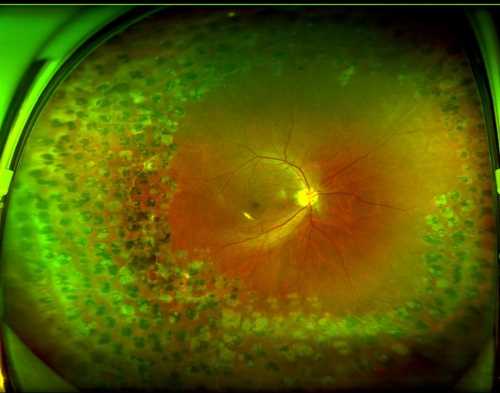

图:张先生右眼眼底